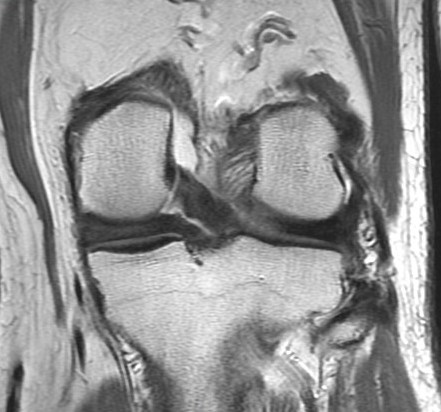

72 y/o M with all over knee pain. No known trauma. R/O meniscus tear.

Root attachment tear of the posterior horn of the lateral meniscus (RID2763)

Much more common to see these medially. These can be mimicked by magic angle but magic angle alone wont result in the irregularity seen here. Also there is some peripheral subluxation of the meniscus suggesting instability. Lateral root tears commonly occur with knee ligament sprains and tears. This patient had a chronic partial tear of the ACL (not shown) Reference article.